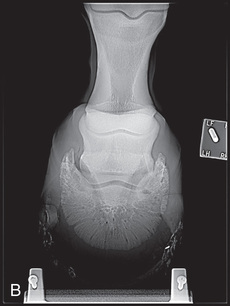

Proper patient preparation is essential to obtain high-quality radiographs and to minimize radiation exposure. The hair coat should be dry, brushed, and cleared of dirt or other debris. If the foot is being radiographed, it is important to prevent overlying shadows superimposed on the field of view. This is especially true of dorsopalmar/dorsoplantar and oblique views. Remove the shoe and trim back any overgrown portions of the foot. Pick and thoroughly clean the sole and clefts, and then pack the sulci adjacent to and in the center of the frog with a substance of similar radiographic opacity, such as Play-Doh, methylcellulose, or softened soap, to eliminate gas shadows due to the grooves of the frog (Fig. 24.2).